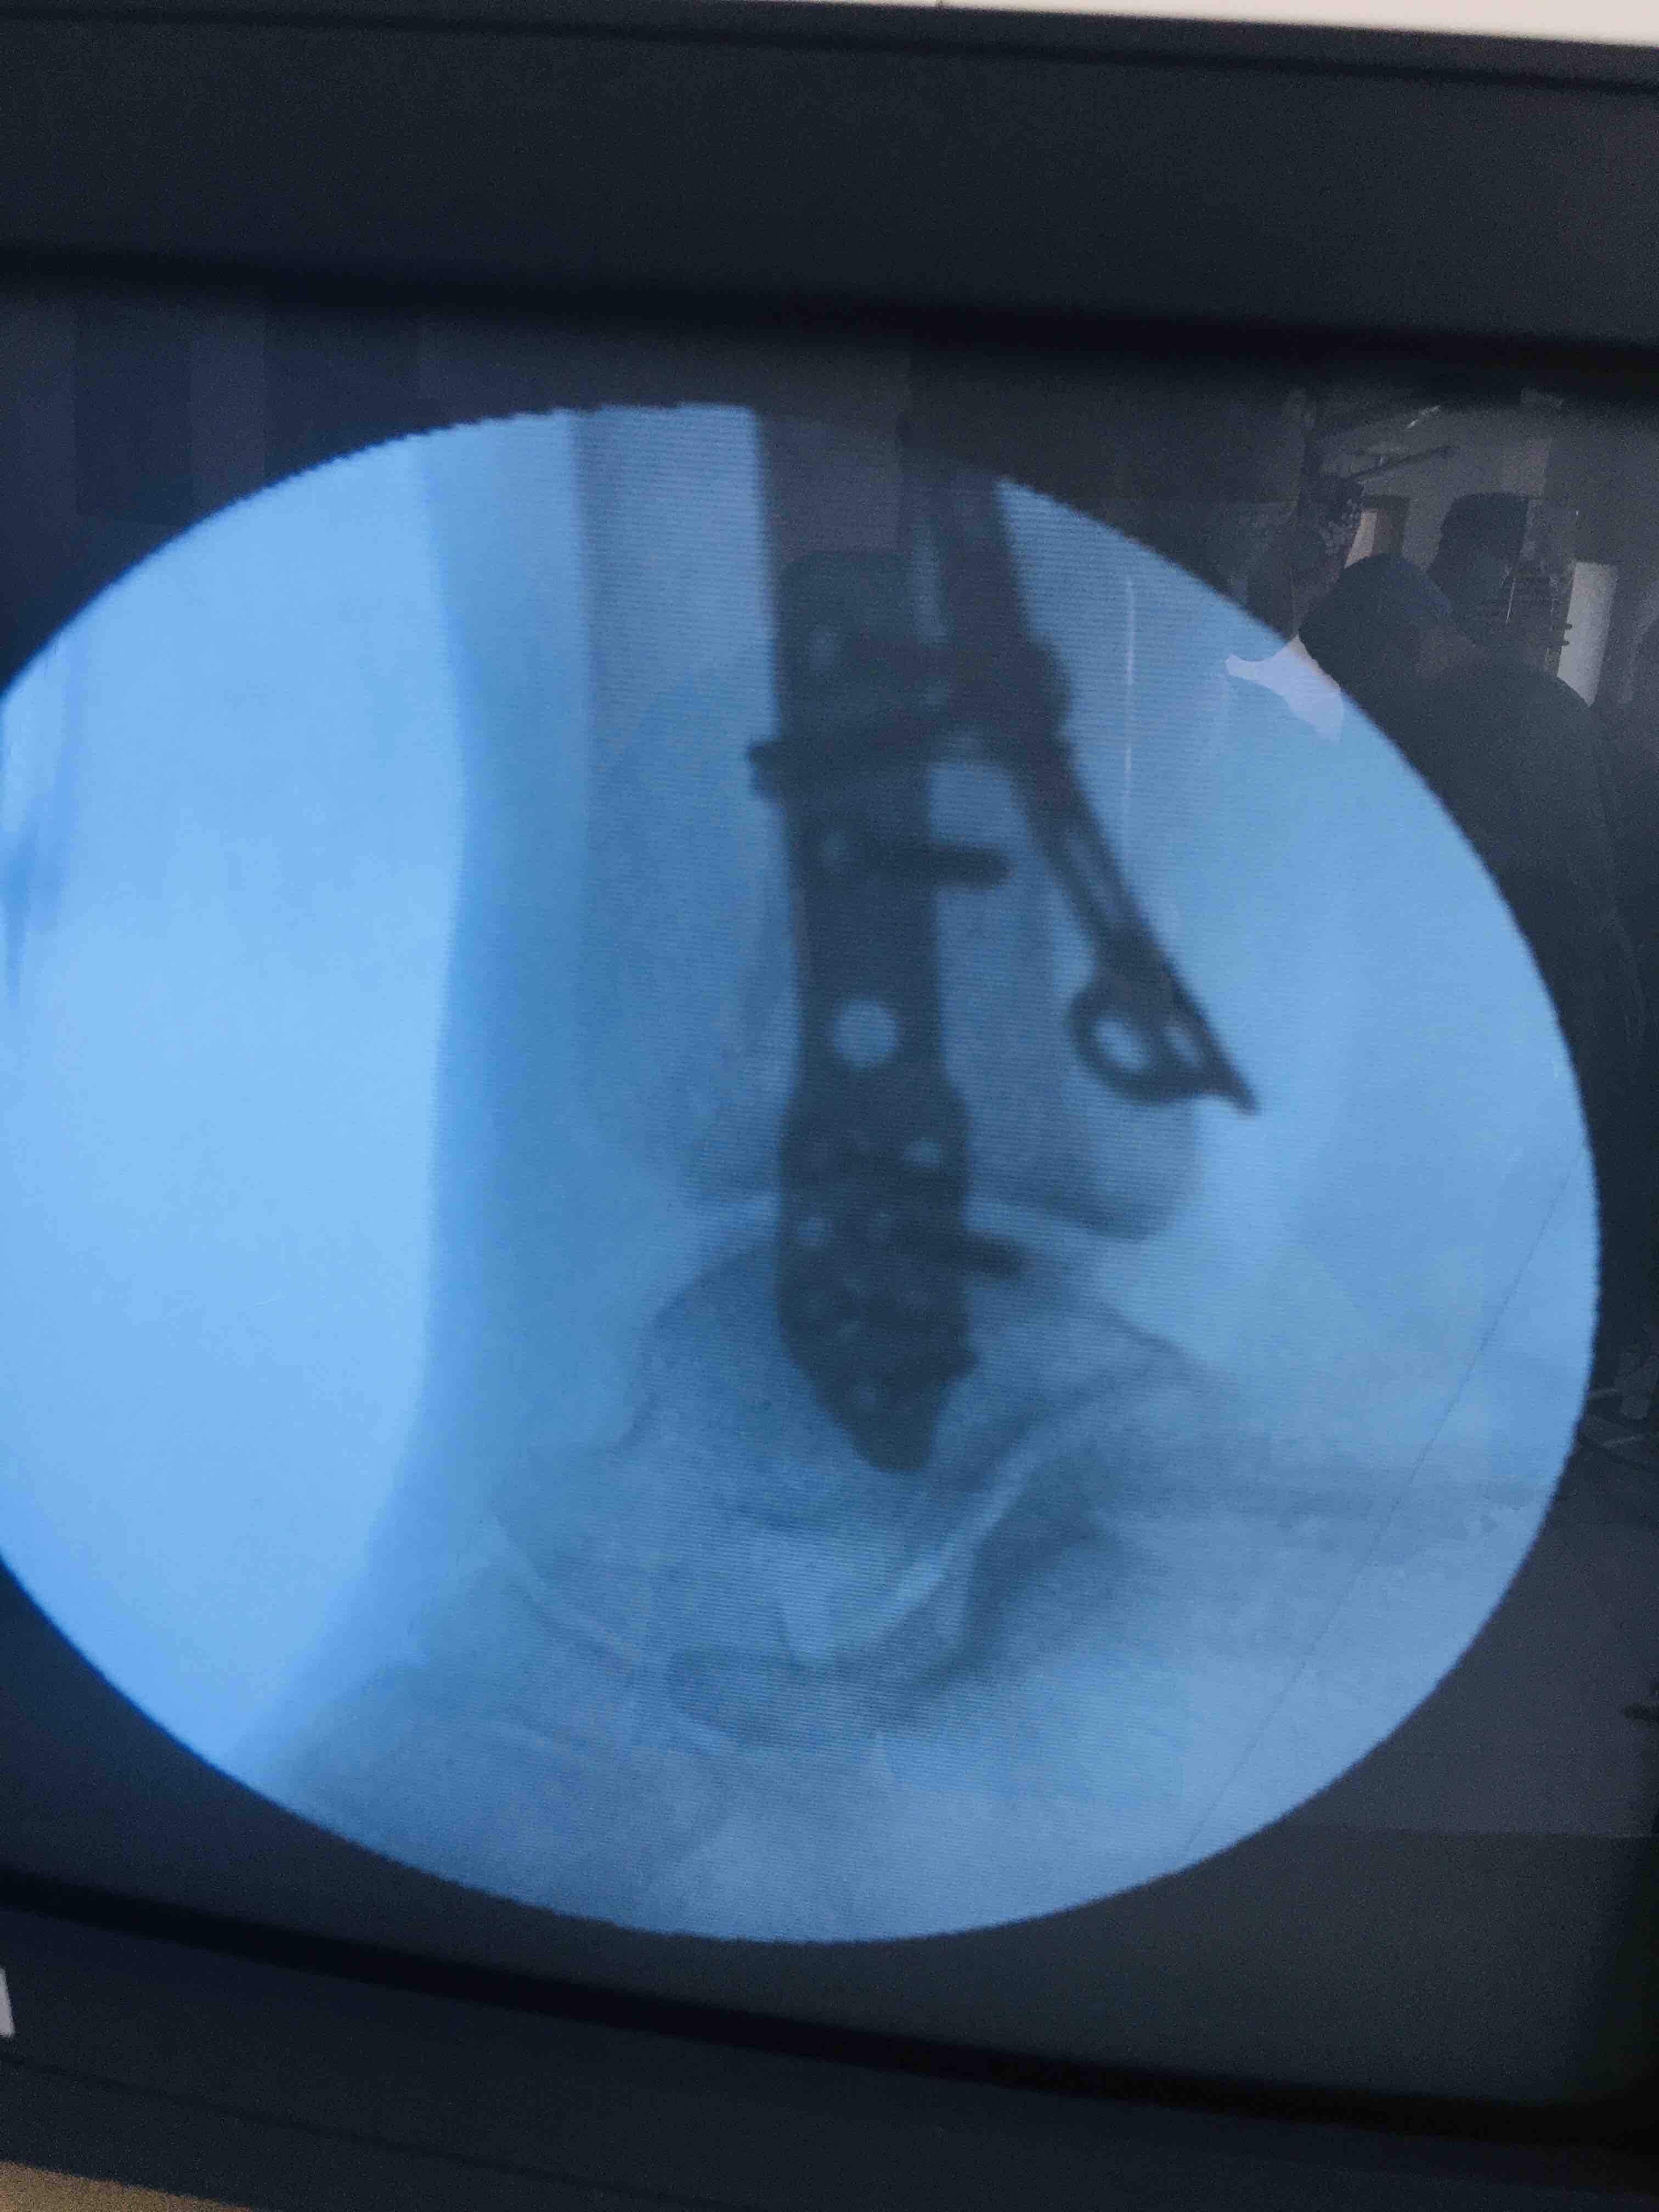

三踝粉碎性骨折(切复内固定术)

摔伤后左踝肿胀,疼痛,活动受限1小时入院。既往身体状况一般。无特殊不良癖好。

生命体征平稳,心肺复未见异常。左踝肿胀明显,畸形,局部皮色发红,皮温高,压痛及纵向叩击痛阳性,末梢血运感觉正常。

急诊行骨牵引,消肿等处理,在腰麻下行切复内固定术,术后抗炎,消肿。